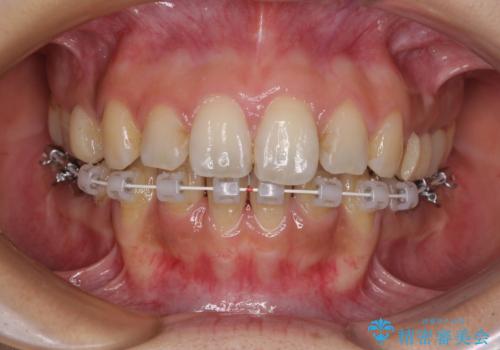

デコボコと口元の突出感 ハーフリンガルでの抜歯矯正

- 矯正装置

- ハーフリンガル

- 前歯のデコボコと上顎の前突感による口の閉じにくさを気にして来院された患者様です。

目立たない装置を希望されたので、上顎が裏側装置のハーフリンガルを選択し、上下左右の小臼歯(計4歯)を抜歯して矯正治療を行うこととしました。